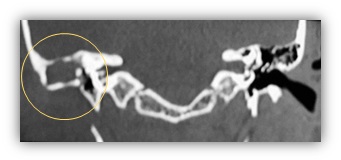

Tomografía simple de oídos con cortes axiales y coronales, en donde se observan celdillas mastoideas derechas poco desarrolladas, no neumatizadas; conducto auditivo sin desarrollo. No se observa adecuadamente la cadena osicular; material isodenso a tejidos blandos, que ocupa el epi-meso-hipotímpano; con resorción del scutum ipsilateral (Imagen 2 e Imagen 3).

Imagen 3: TC simple de oídos, corte coronal; se observa ocupación de epi-meso-hipotímpano por lesión isodensa a tejidos blandos.